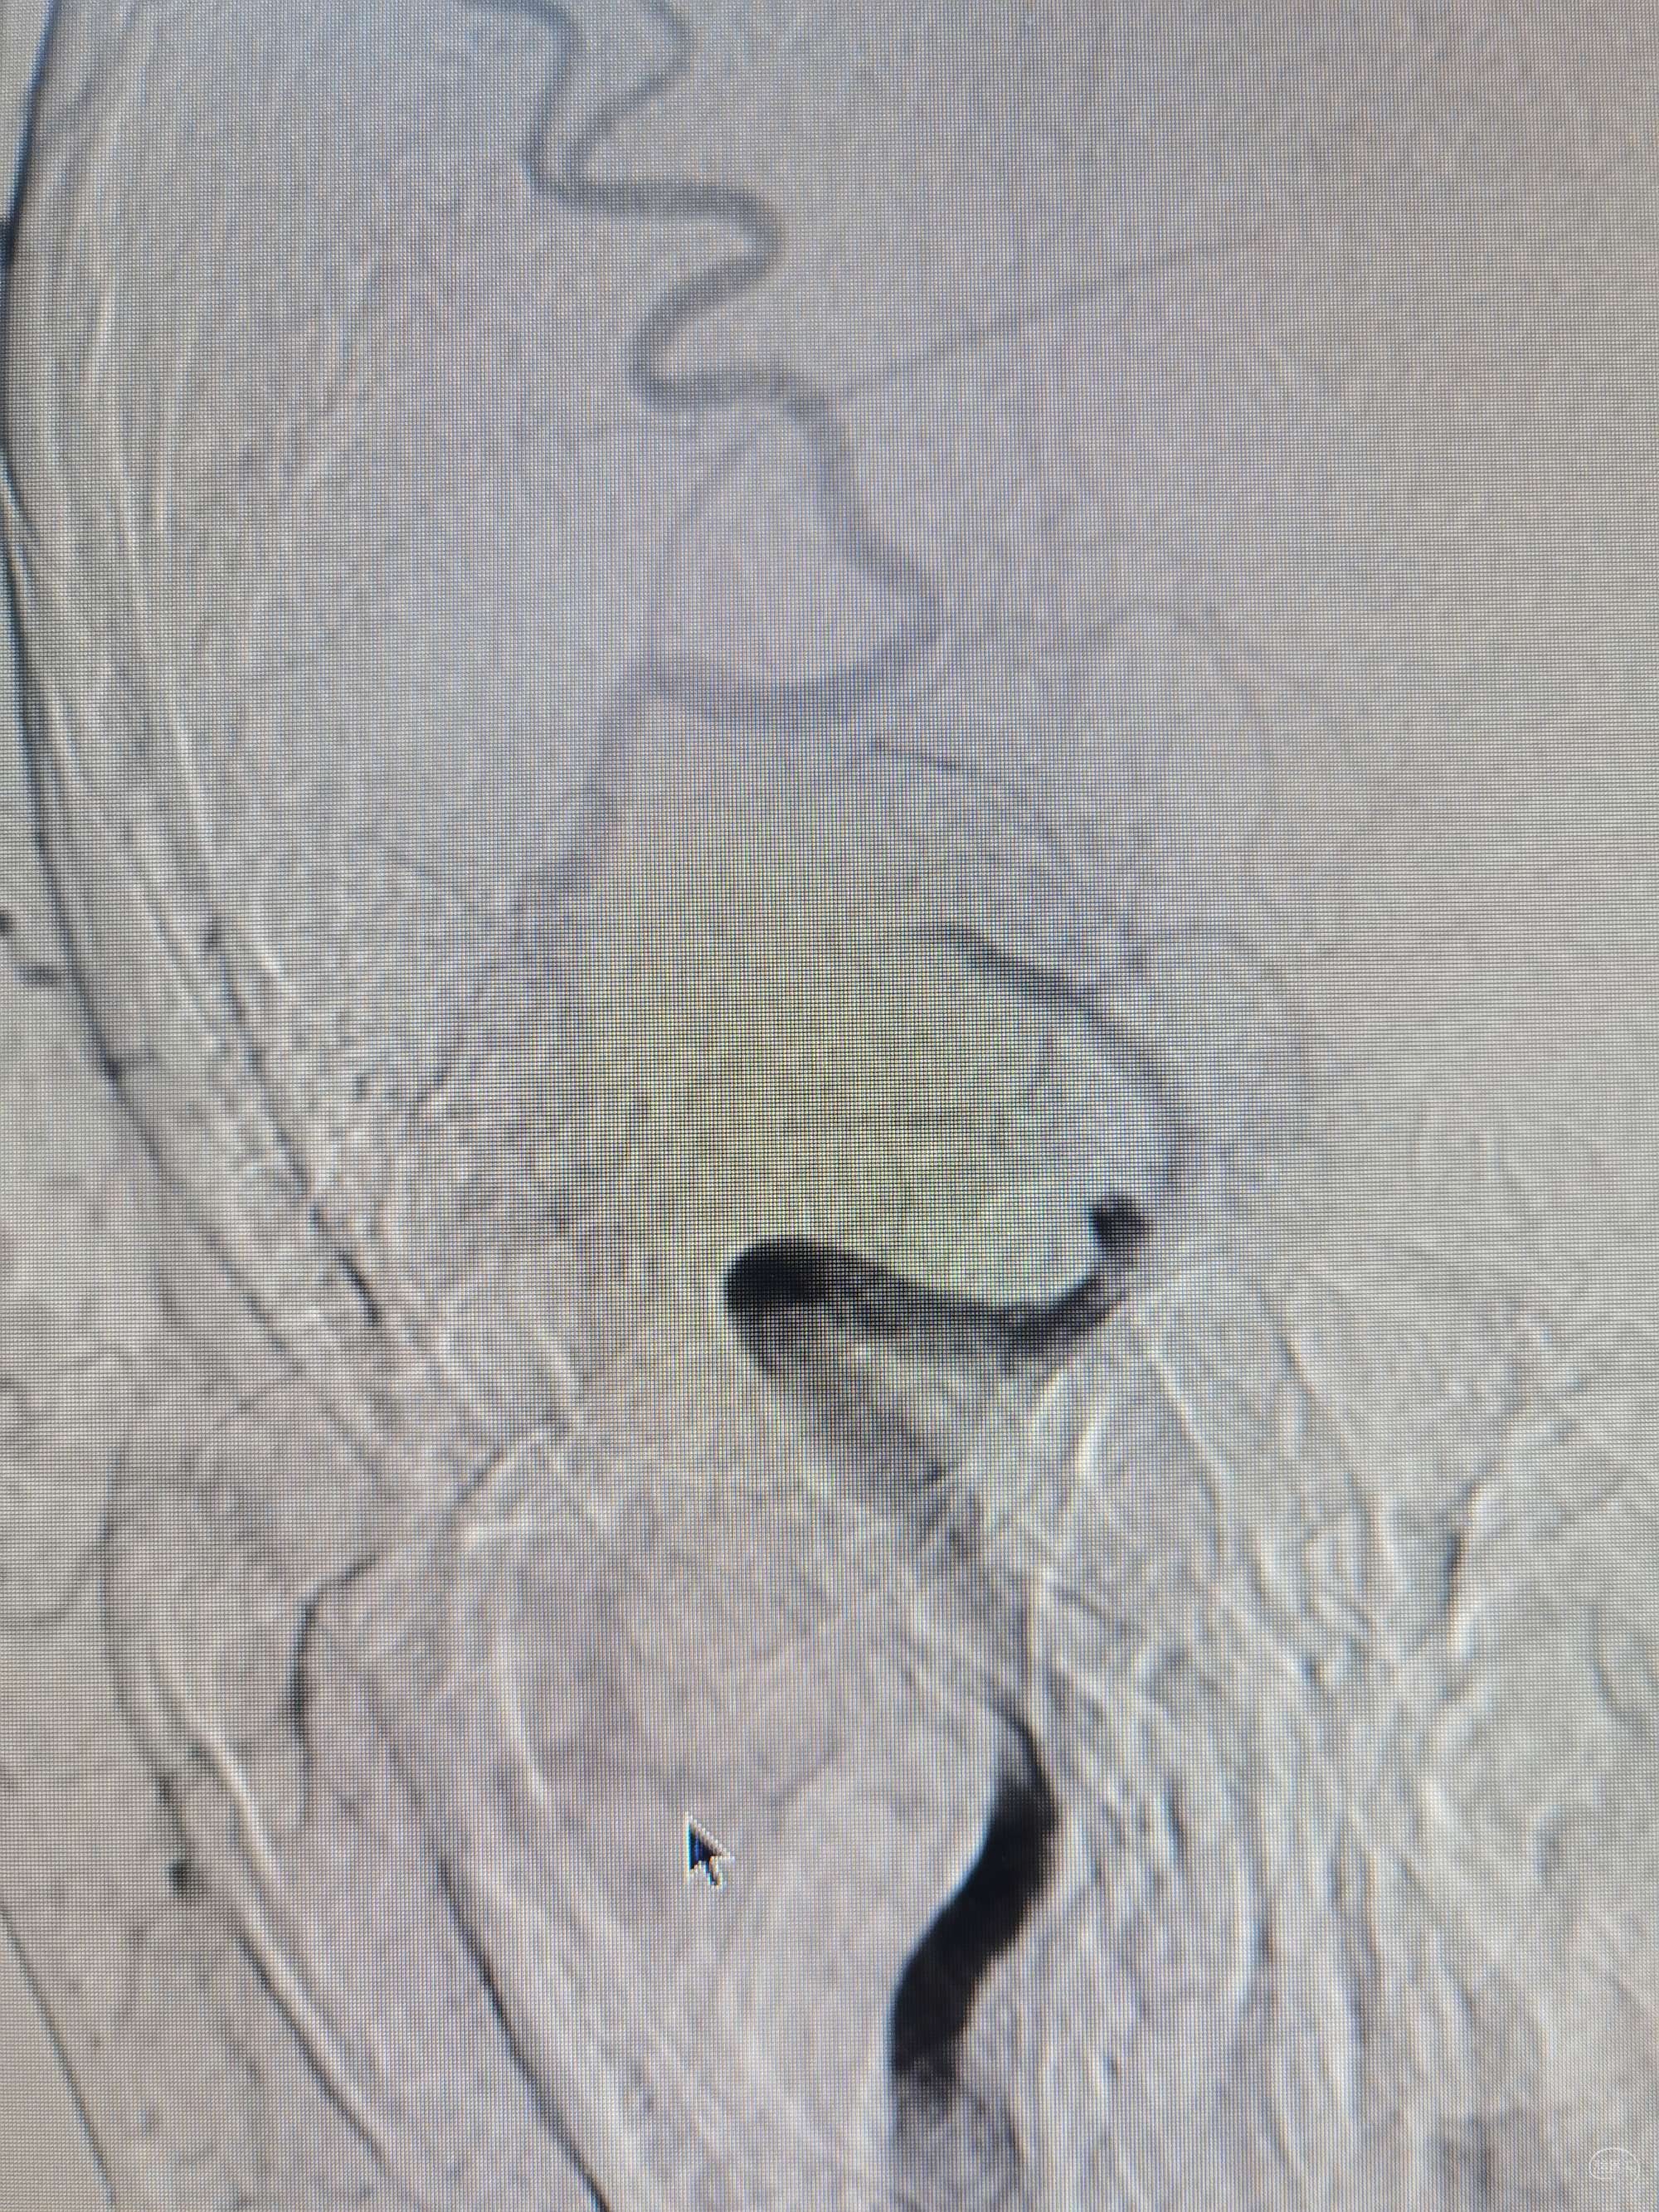

右侧颈内动脉正位:m1段闭塞(看看形态,不太像栓塞的表现)